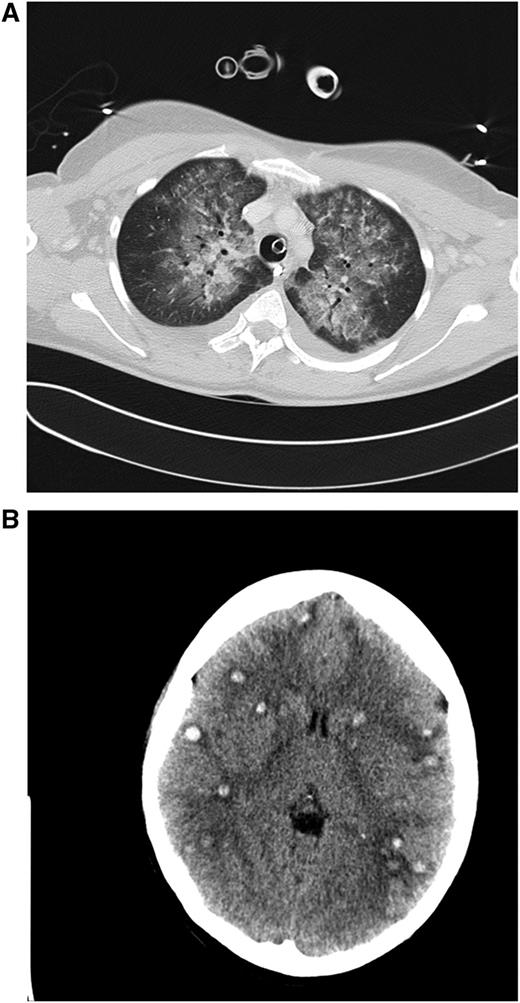

Clinical case 1. A 42-year-old woman presented to her general practitioner with general weakness and tooth pain. Laboratory assessment showed a WBC count of 80 000/µL, hemoglobin of 6.4 mg/dL, and platelet count of 21 000/µL, which led her physician to make an immediate referral to the local hospital, where a differential blood count revealed 56% myeloid blasts. By that time, the patient was in stable clinical condition with a minimally elevated C-reactive protein of 20 mg/L. She was put on 4 g hydroxyurea (HU) and planned for transferal to our hospital the next morning. During the night, she developed dyspnea requiring oxygen supply. We diagnosed an AML M4eo with inv(16) and started induction treatment with cytarabine plus daunorubicin (7 + 3) at a WBC count of 70 000/µL. Immediate leukapheresis was not possible because of the progressive dyspnea and the increasingly deranged coagulation status. By the next day, the WBC count had gone down to 19 000/µL, but the patient developed respiratory failure requiring mechanical ventilation. The computed tomography (CT) scan result was highly suggestive for leukostasis of the lungs (A), and cranial CT showed multiple focal supratentorial hemorrhages (B). During the next few days, respiratory indices improved, and the patient could be extubated. Early bone marrow response assessment showed a good response with leukemia-free hypoplastic marrow, and after regeneration of peripheral counts, a complete remission (CR) was diagnosed. The patient has currently completed consolidation chemotherapy and is in ongoing CR. The remarkable aspects of this case are (1) the fact that leukostasis developed rapidly even at a WBC count below 100 000/µL, possibly because of the monocytic nature of blasts11 ; (2) cytarabine alone led to a profound and rapid WBC reduction; and (3) the patient recovered from mechanical ventilation because the underlying leukostasis could be treated successfully. (A) Contrast-enhanced CT image (lung window) through the upper fields of the lungs demonstrates parenchymal infiltrates as well as diffuse ground-glass opacities suggestive for leukostasis and myeloblast infiltration. There is sparing of the lung periphery. Note also bilateral pleural effusions. Respiratory failure required mechanical ventilation support as indicated by the endotracheal tube. A central venous catheter in the right brachiocephalic vein and nasogastric tube in the esophagus can be seen. (B) Horizontal plane of native cranial CT scan demonstrating multiple hyperdense lesions in both brain hemispheres indicating hemorrhagic lesions. Accompanying cerebral edema is characterized by loss of gray-white matter differentiation, compression of lateral ventricles, and effacement of sulcal spaces.